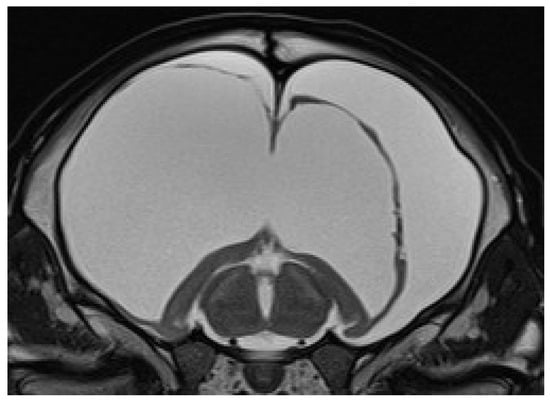

4.6. Imaging

Eleven calves underwent MRI. Imaging identified different stages of cortical parenchymal loss affecting both white and gray matter throughout the hemispheres in all 11 calves (Table 1). The cerebral hemispheres were reduced to a thin rim of tissue in six cases. The remaining cavity was filled with cerebrospinal fluid by a secondary enlargement of the lateral ventricles (Figure 2). These findings are consistent with hydranencephaly. In three cases, there was a severe enlargement of the ventricular dimensions and residual gyrated cerebral tissue was visible, consistent with severe internal hydrocephalus (Figure 3). Two calves showed no or only mild ventricular enlargement with normal gyration of the cerebral tissue. In these two cases, a reduced contrast between white and gray matter was noticeable and focal hyperintense areas in the white matter were visible. Impaired cerebral myelination or focal leukomalacia were suspected.

Figure 2. Transverse T2-weighted MRI of a brain at the level of the thalamus and hippocampus of a 24-day-old male calf with obtundation, absent menace response, proprioceptive ataxia, and proprioceptive deficits. Note the absence of the cerebral hemispheres with a small cortical rim and preserved hippocampal structures and the bilateral severe enlargement of the lateral ventricles, suggesting hydranencephaly.